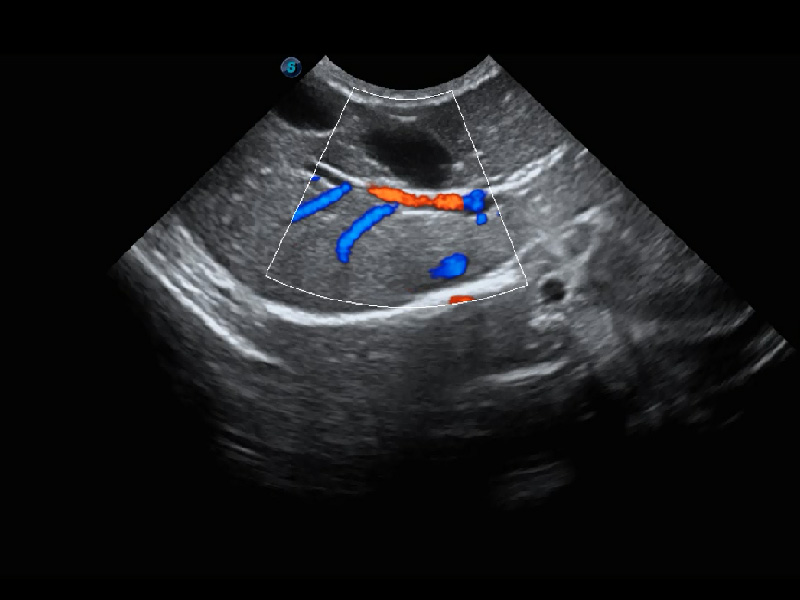

ProPet 60 作為一款高端臺式動物超聲設(shè)備,為動物醫(yī)生的日常診斷提供了一系列貼合動物臨床需求、解決臨床實際問題的高級成像功能。憑借全系列高清探頭,滿足醫(yī)生對腹部、心臟、生殖、淺表、肌骨等成像的所有需求,切實幫助您提升檢查效率,提高診斷信心。